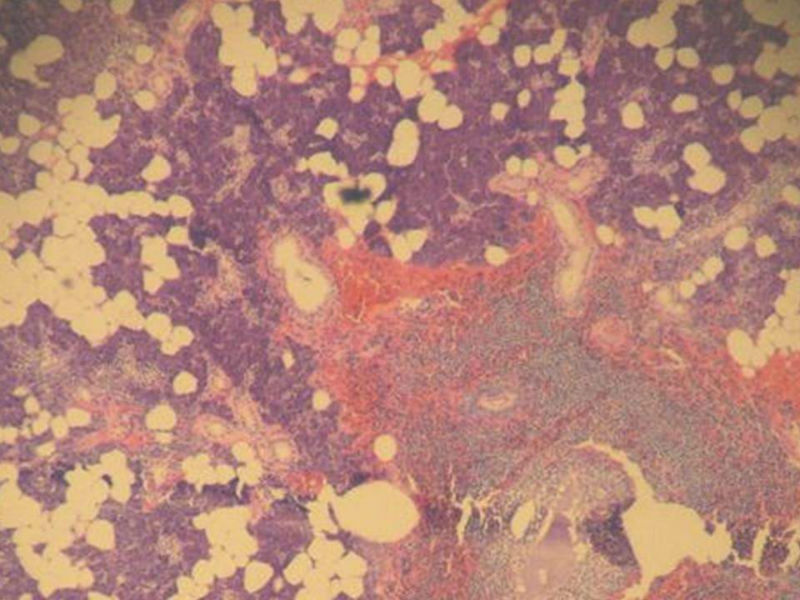

腮腺肿物:良性淋巴上皮病变(Mikulicz病)

女,71岁,腮腺肿物,临床诊断混合瘤。